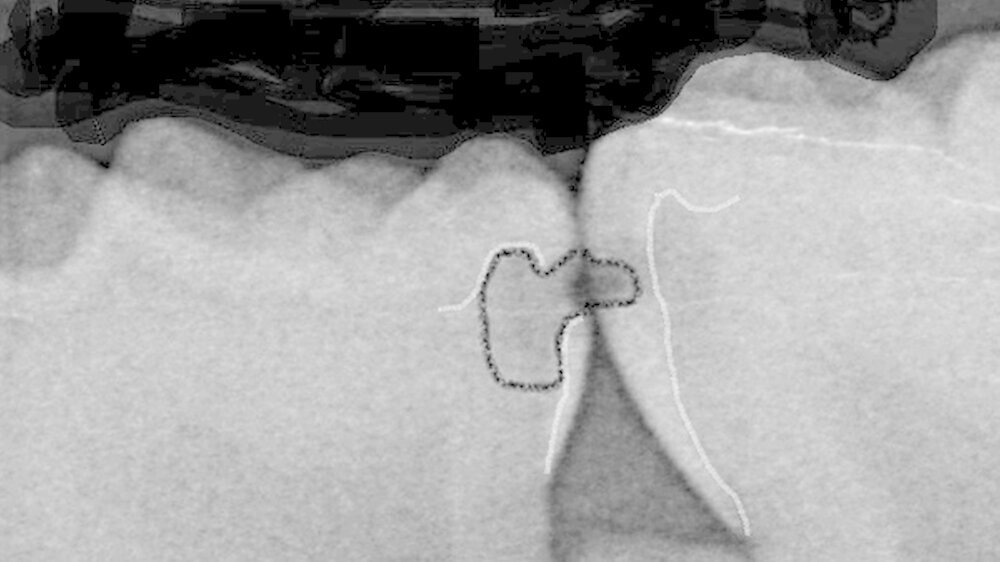

Zuerst ist fast immer der Vierer distal betroffen, dann folgt der Fünfer mesial. Milchzähne haben durchschnittlich nur eine Schmelzdicke von einem Millimeter, der Schmelz am Vierer distal ist noch dünner, das heißt noch anfälliger. Der Kontaktpunkt 4/5 bildet sich erst in der Gebrauchsphase des Milchgebisses, wobei er zusätzlich häufig flächiger wird. Die anderen Kontaktpunkte im Milchgebiss lösen sich durch die physiologische Lückenbildung eher auf, das Kontaktpunktkariesrisiko sinkt also.

Wie wichtig ist die Bissflügelaufnahme für die Diagnose?

Ich mache immer mehr Bissflügelaufnahmen und immer früher. Denn erkenne ich eine initale Karies früh, kann ich diese mit den Eltern zusammen ausheilen, sprich eine Füllung beziehungsweise abhängig vom Alter und der Kooperationsbereitschaft des Kindes eine Sanierung in Narkose verhindern. Das Röntgenbild zeigt den Eltern das Problem und hilft mir, sie für die Verwendung von Zahnseide zu gewinnen.